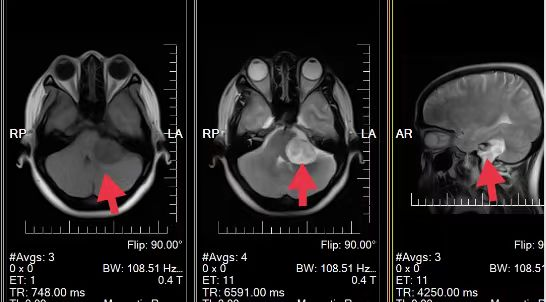

09、**女士,36岁

于2023年11月10日在邢台仁泰体检部体检,颅脑MRI提示:左侧CPA长径约4cm大小不规则占位性病变、包膜完整信号不甚均匀,呈稍长T1稍长长T2-FLAIR改变。瘤周无水肿、占位征象明显、局部小脑、延髓明显受压变形移位。2023年11月10日电话通知,建议客户去三甲医院进一步检查,2023年11月17日跟踪回访,客户已到北京天坛医院就诊,考虑脑部占位性病变,已住院手术。